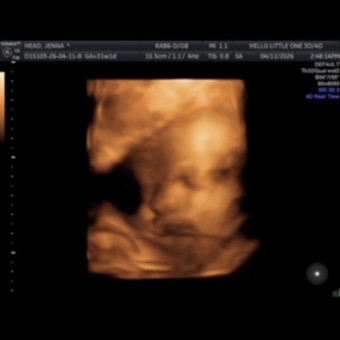

Hey everyone. We are so excited to bring our little girl into the world. We are extremely grateful for anything you give us! These are just some ideas of things we may need or want. Thank you for spoiling our little girl laurenna already.